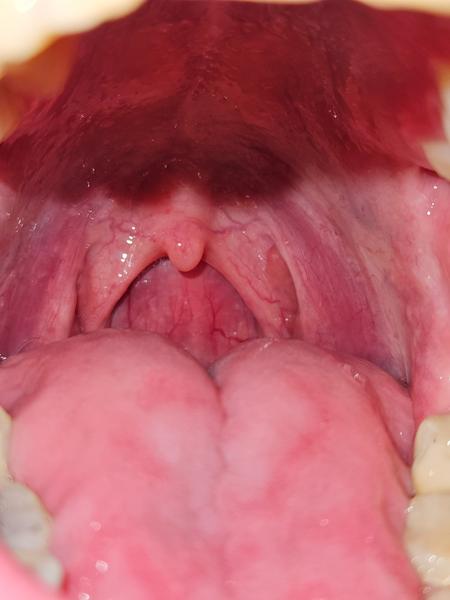

Ako vyzera hrdlo? Mam zapálené? Čo to môže byť? Poraďte.